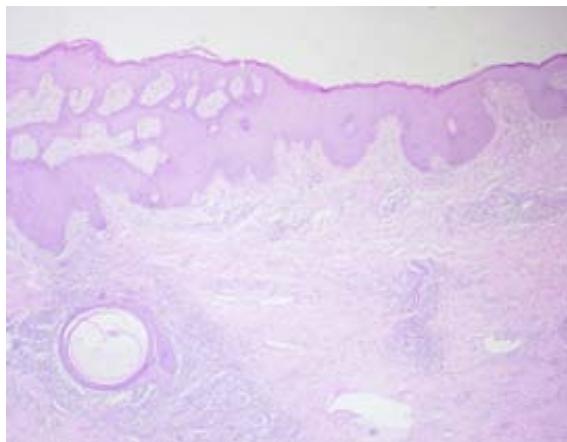

The skin biopsy of the right axillary region showed epidermis with pseudoepitheliomatous acanthosis, a dense inflammatory infiltrate made up of lymphocytes, plasma cells and histiocytes, permeated by some neutrophils and rare osinophils in the dermis. No parasites were found in the skin fragment evaluated. An excisional biopsy of the right inguinal lymph node showed reactive lymphadenopathy with a pattern of follicular and paracortical hyperplasia, with no evidence of neoplasia.

Fig. 4: Reactive lymphadenopathy with a pattern of follicular and paracortical hyperplasia, with no evidence of neoplasia

C Fig. 5: (A) Lower magnification showing epidermis with irregular pseudoepitheliomatous acanthosis; (B and C) Dense inflammatory infiltrate made up predominantly of lymphocytes, plasma cells and histiocytes, permeated by some neutrophils and rare eosinophils, with no signs of parasites